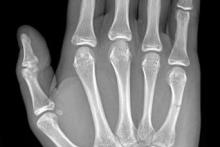

16-latek po urazie śródręcza prawego

Przypadek 61: 16-latek po urazie śródręcza prawego - przypadkowe uderzenie w słup.

Rozpoznanie: Złamanie środkowej części trzonu 5-ej kości śródręcza, z ugięciem odłamu dystalnego.